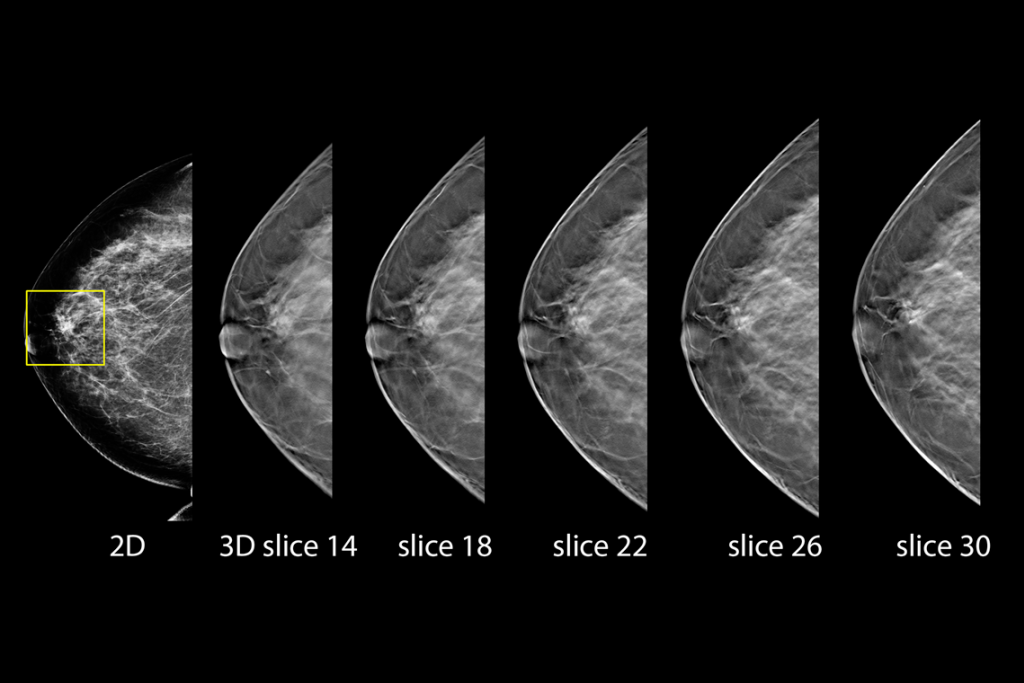

Imagens clínicas de mamografia